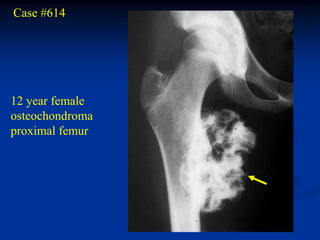

Case #614

12 year female

osteochondroma

proximal femur